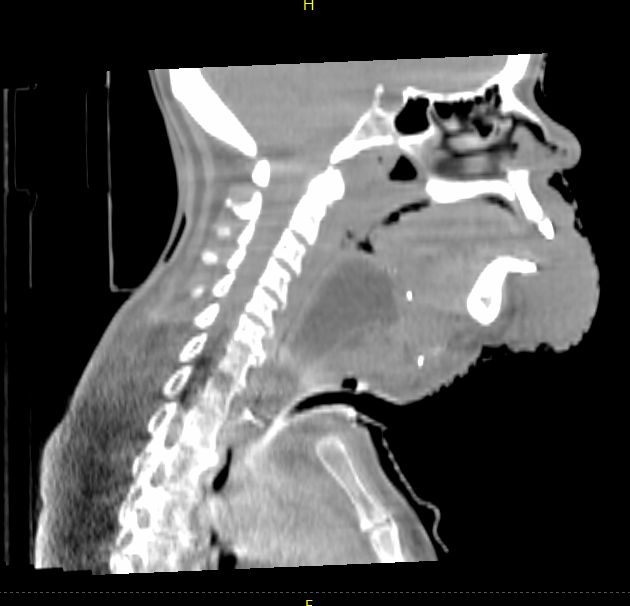

Images above acquired on TrueBeam, courtesy of UH Seidman Cancer Center, Cleveland, Ohio

Head and Neck

In this head and neck case with extensive disease involvement, the larger FOV delivered by HyperSight on a Varian TrueBeam system provides greater visibility of the structures and organs surrounding the target to enable a more accurate positional alignment. In this case, the clinician is able to visualize all pertinent anatomy without the need to acquire additional images. This potentially means less time on the treatment couch, less time in the immobilization device, and less imaging dose to the patient.